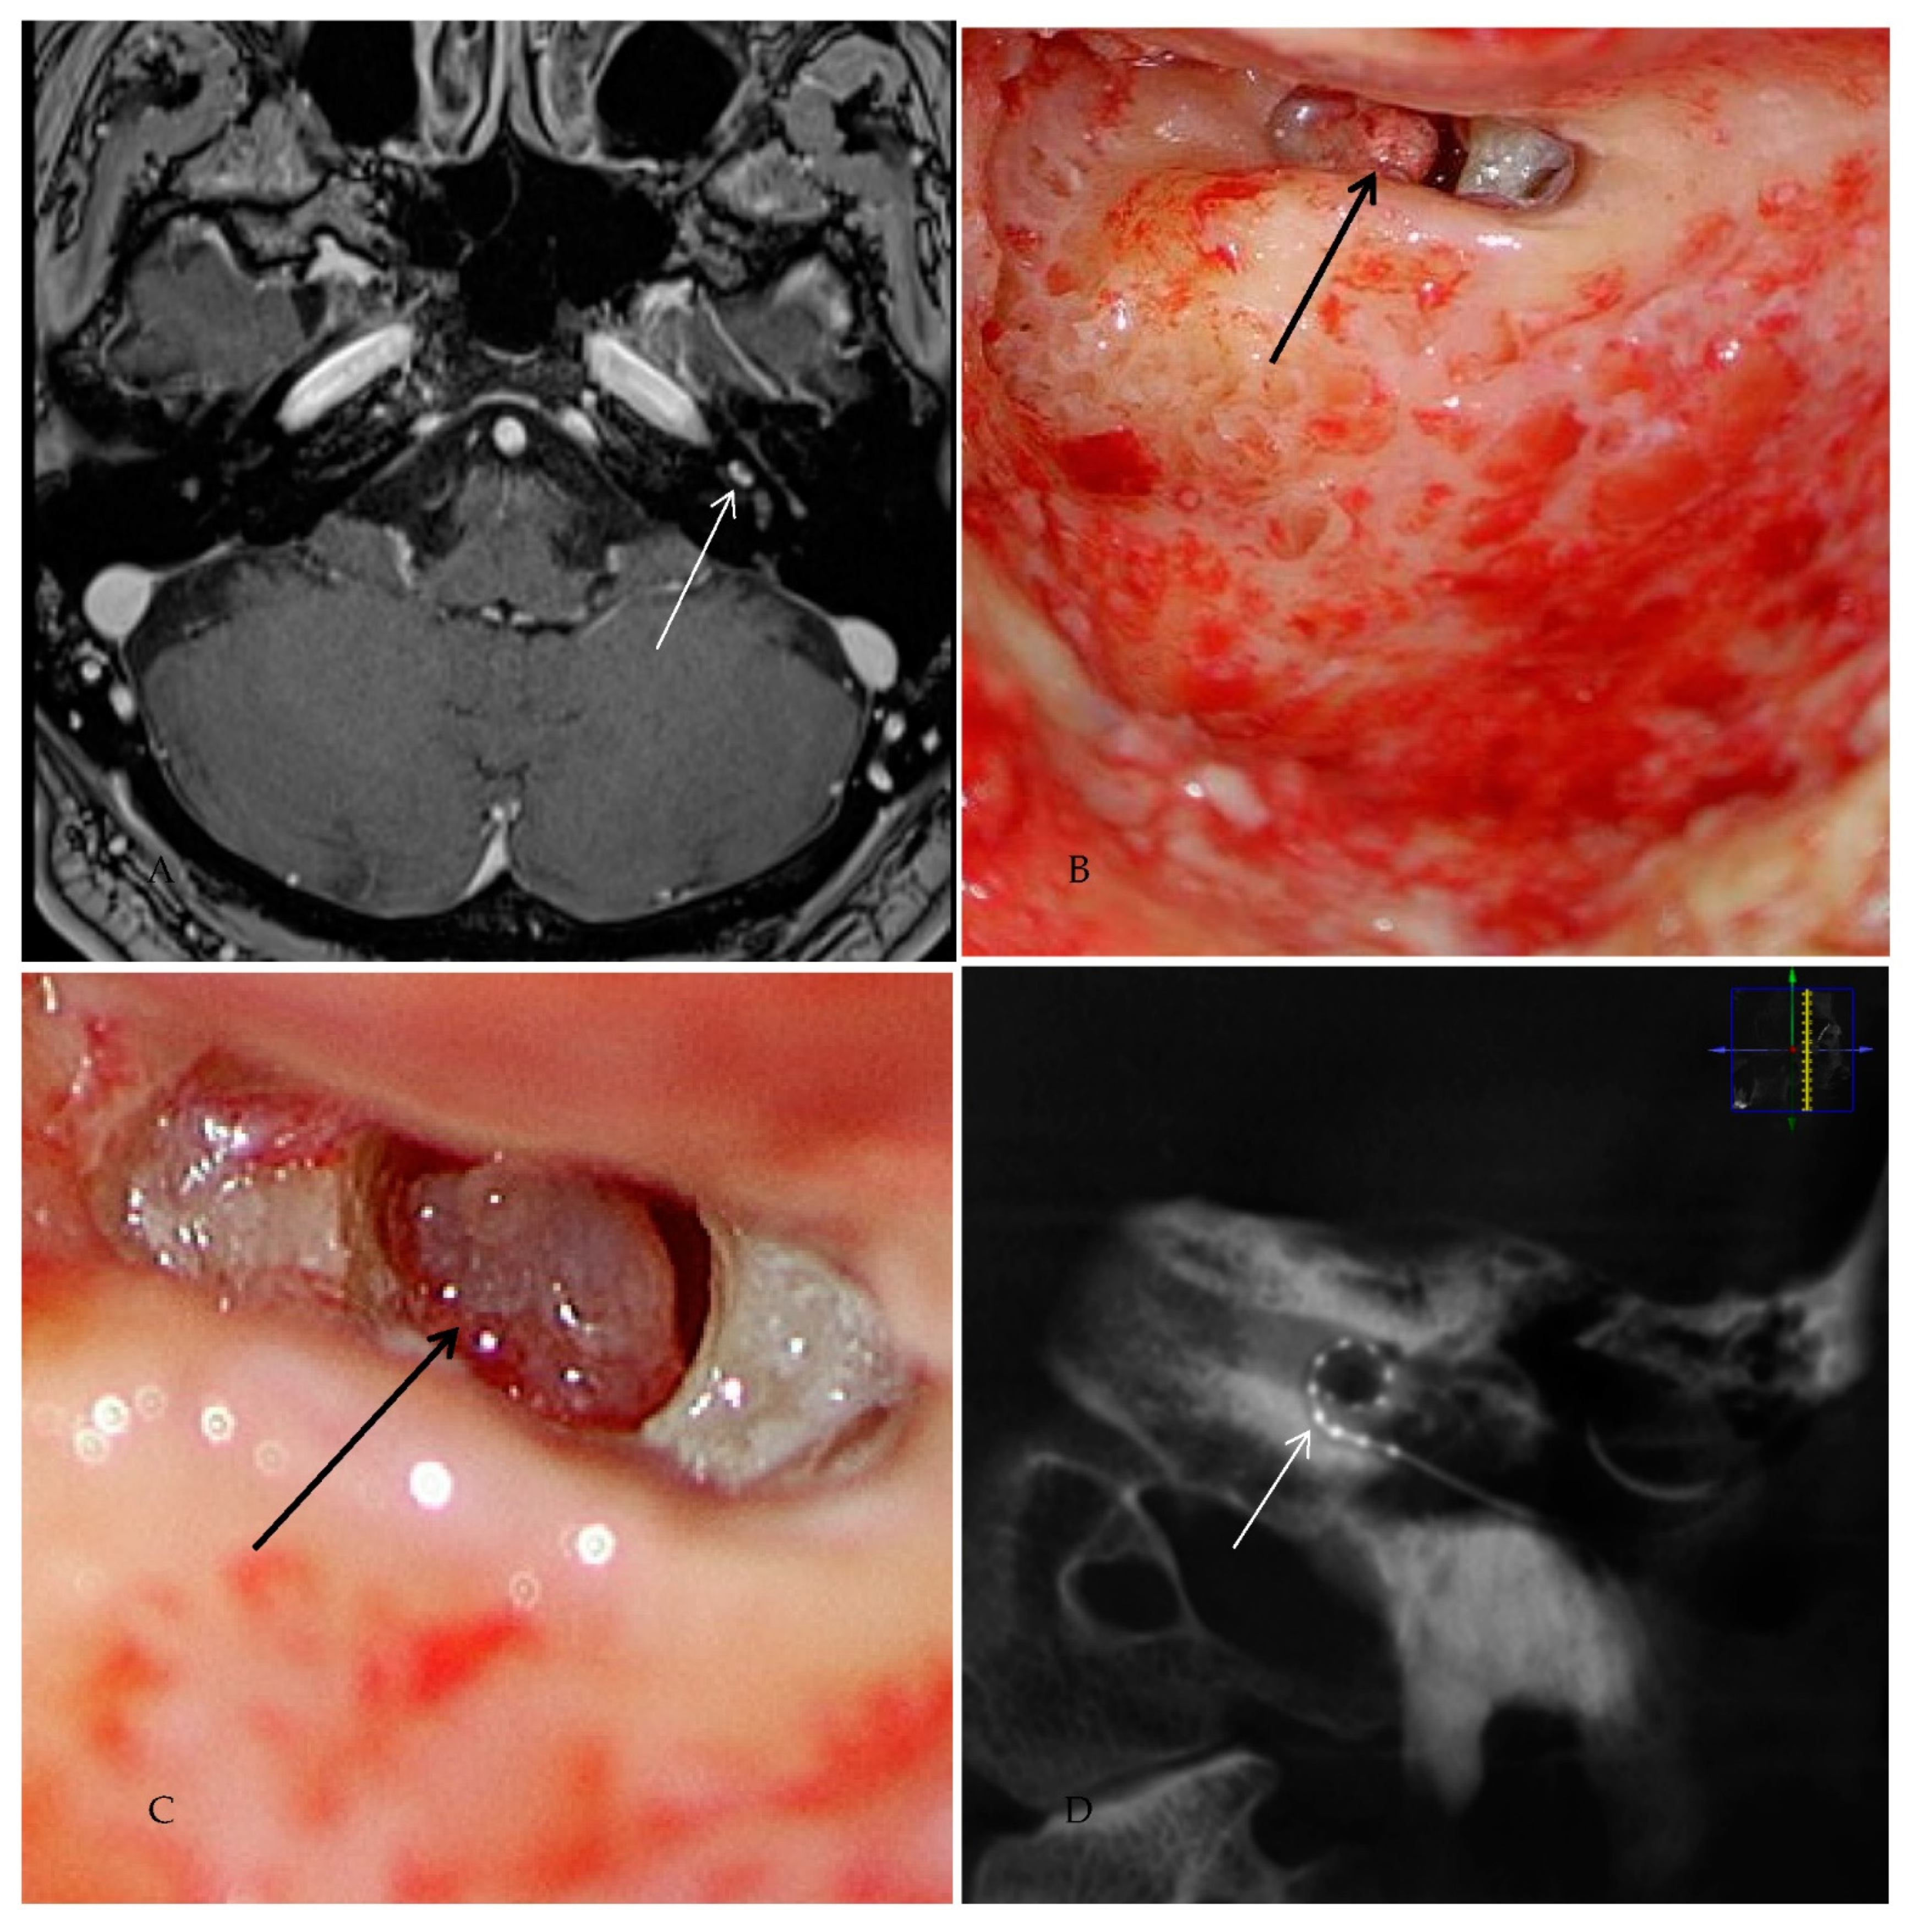

Patient #1 had a vestibulocochlear type of ILS. The tumor extended from the basal cochlear turn towards the vestibulum, ampulla of the superior and horizontal semicircular duct, and the common crus (Figure 2A–D). Tumor resection was performed with an extended round window and a translabyrinthine approach.

Figure 2. cMRI imaging (Case #1). Shown are T1 weighted images with i.v. gadolinium, fat-saturated, 2 mm. The tumor had a vestibulocochlear extension from the basal turn of the cochlea to the vestibulum and ampulla of the superior and horizontal semicircular duct and their common crus. Blue arrow: venous cerebellar malformation. (A) Contrast-enhanced visualization of ILS in the basal cochlear turn (white arrow). (B) ILS in the basal cochlear turn and the ampulla of superior/horizontal semicircular duct (white arrow). (C) ILS in the ampulla of superior/horizontal semicircular duct (white arrow). (D) ILS in the common crus of the superior and horizontal semicircular duct (white arrow).